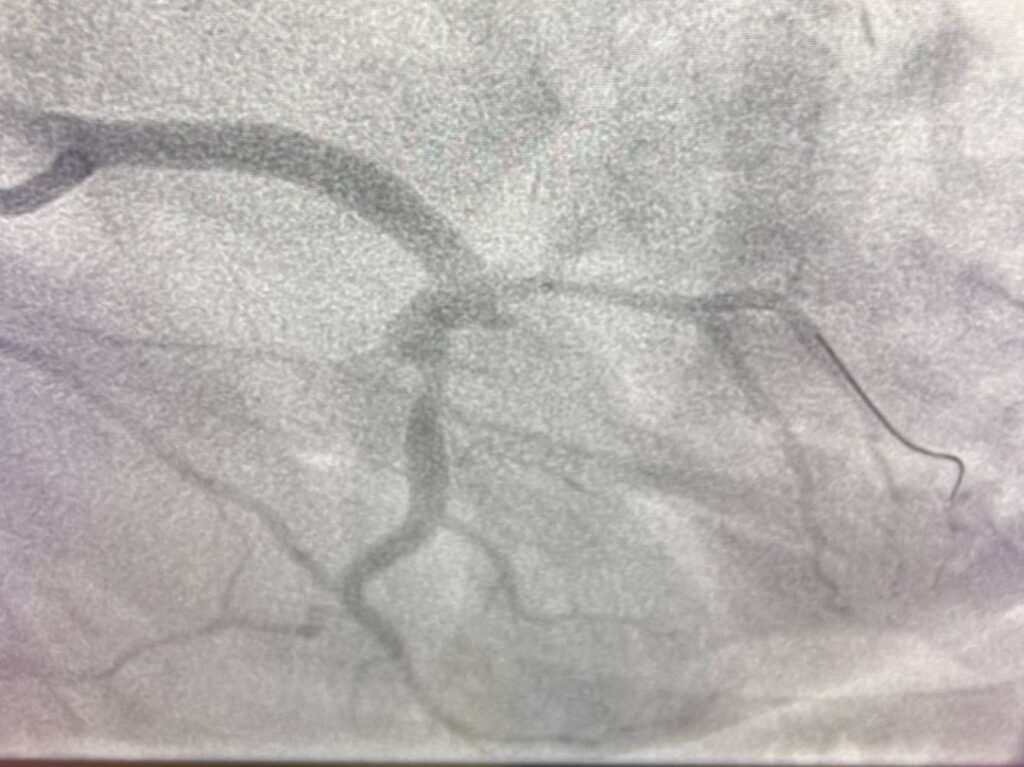

El Hospital público Universitario de Torrejón, perteneciente a la red pública de la Comunidad de Madrid, ha intervenido con éxito a un varón joven con un aneurisma coronario gigante de casi 10 centímetros, una dilatación anormal de una arteria del corazón que, por su tamaño, comprimía las propias arterias coronarias, que son los vasos que llevan la sangre al corazón, y le provocaba angina (dolor en el pecho), poniendo, por su peligrosa localización, potencialmente en riesgo su vida.

Por otro lado, se trató la exclusión del aneurisma mediante un stent cubierto (graft) de alta especialización, sellando la dilatación gigante que afectaba al tronco de la coronaria izquierda y a sus principales ramas: descendente anterior, bisectriz (ramus) y circunfleja. Tras la operación, el paciente ha evolucionado favorablemente y ya se encuentra en su domicilio.

Un aneurisma coronario es una “bolsa” o dilatación que se forma en una arteria del corazón. Aunque las coronarias miden solo unos milímetros de diámetro, en este caso la dilatación alcanzó casi 10 centímetros.